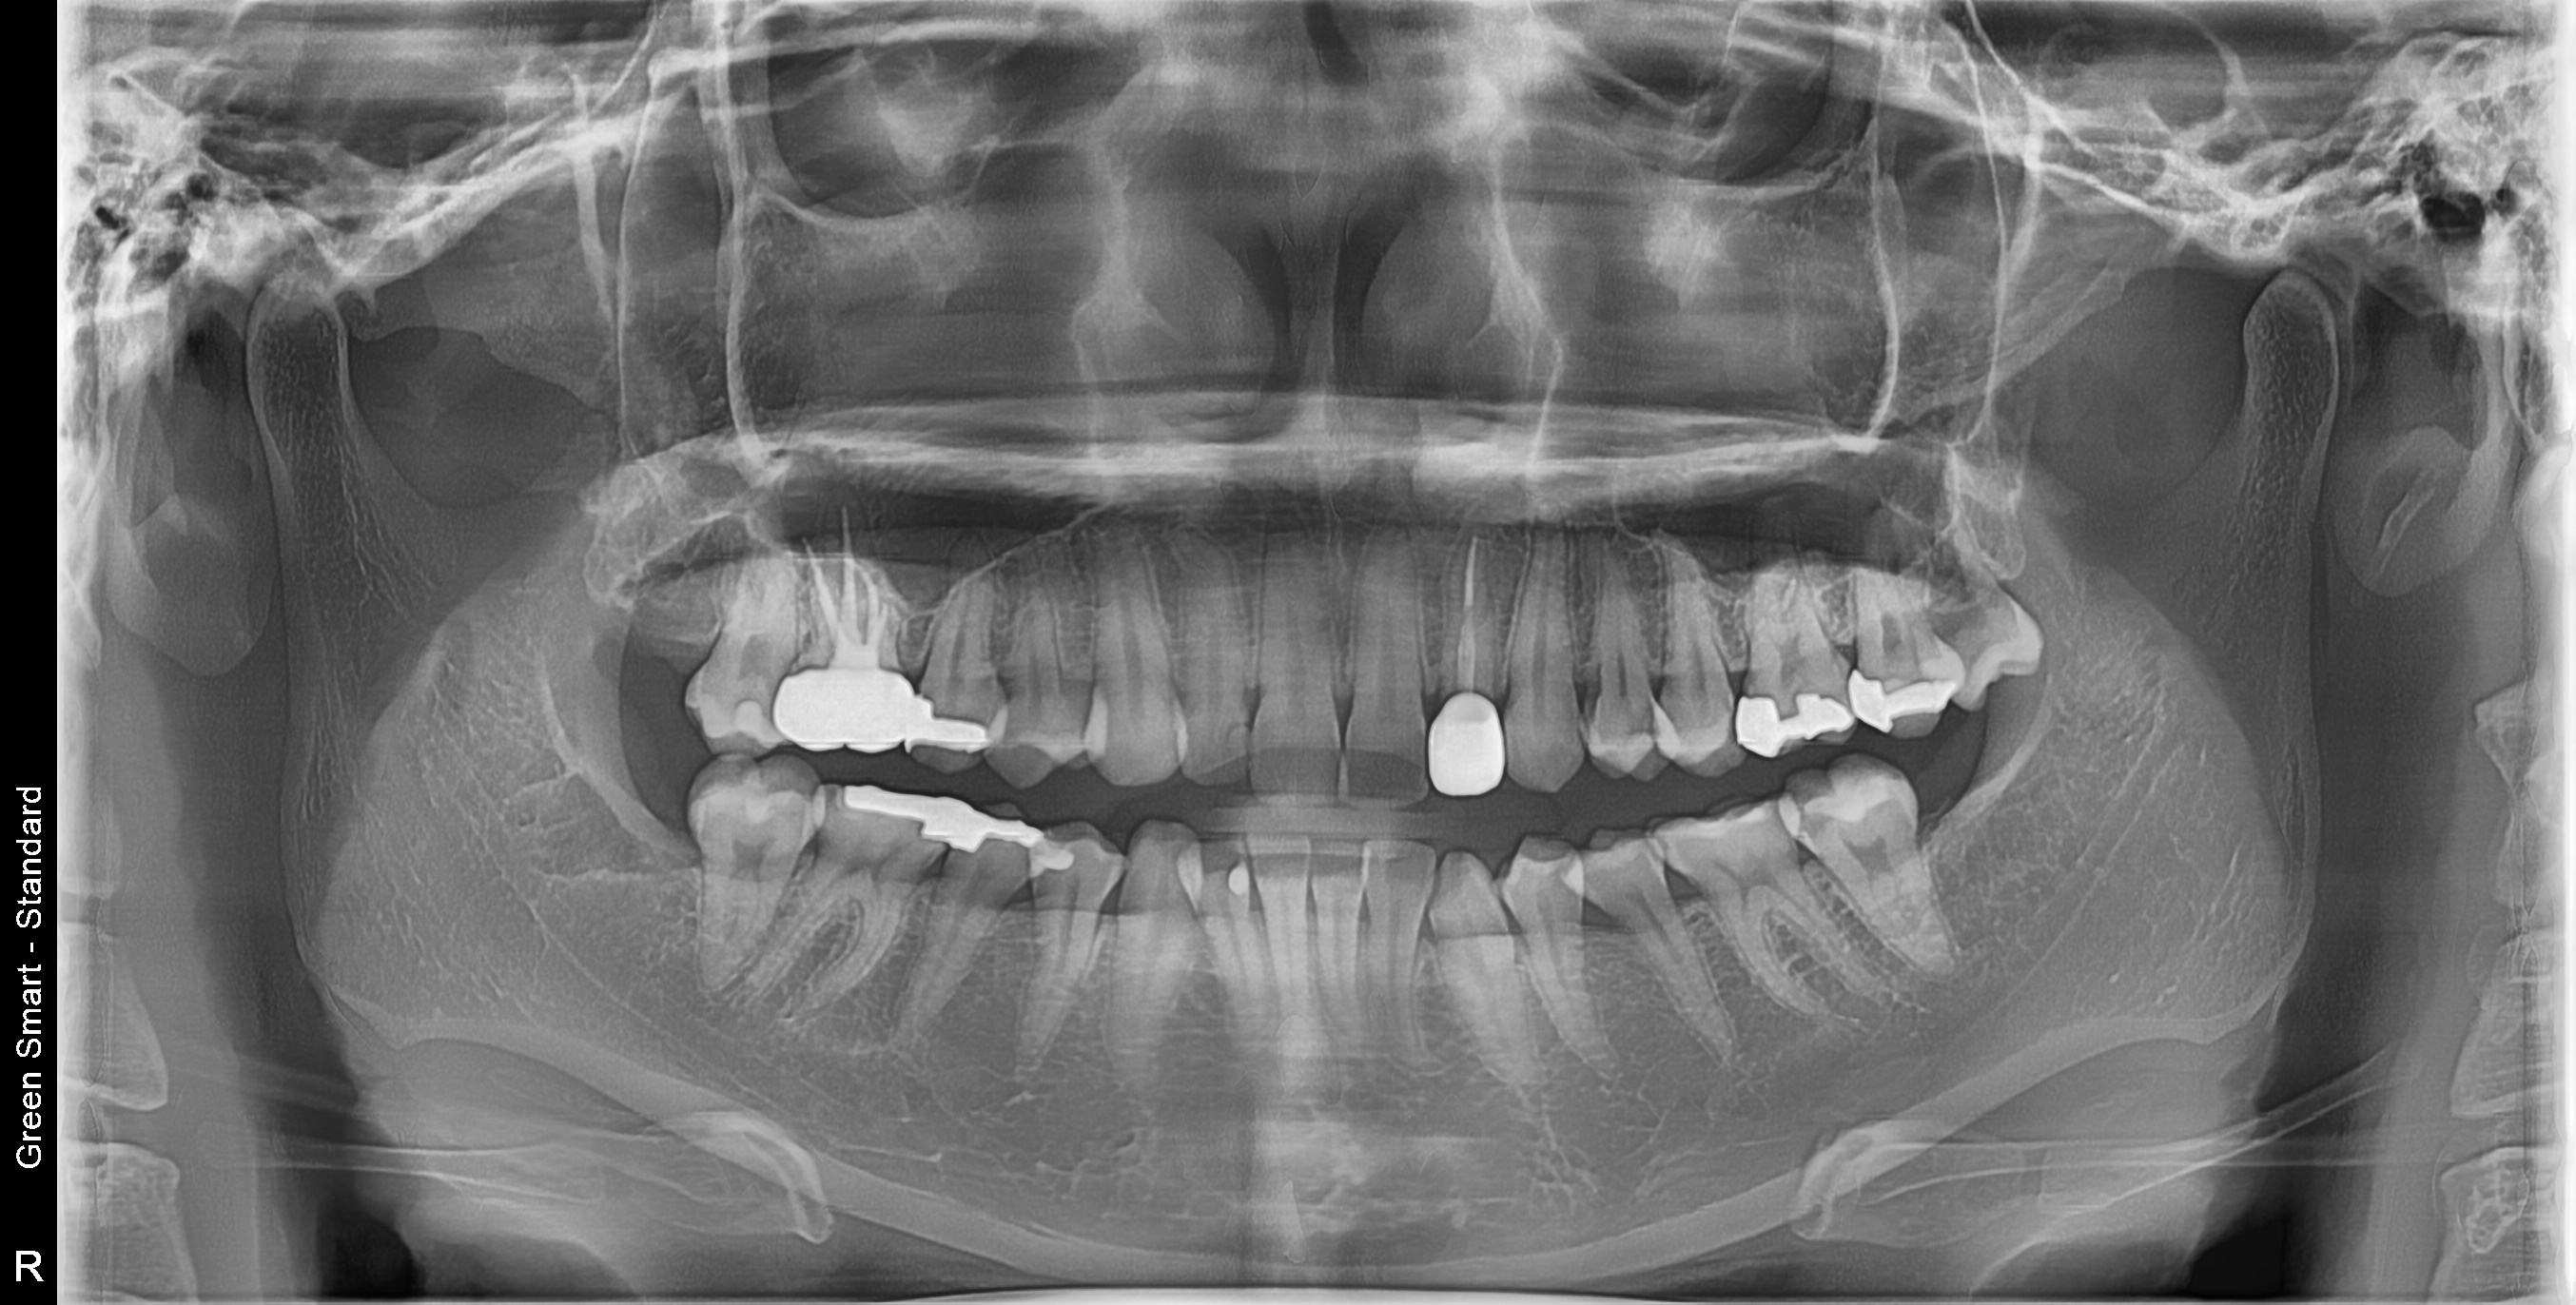

우리 병원 사랑니 발치의 특별함

2,700건 이상의 사랑니 발치 경험과 체계적인 시스템으로 차원이 다른 진료를 합니다

대학병원급 난이도 발치

일반 치과에서 "큰 병원 가보세요", "전문병원에서 빼세요" 이런 말 들어보셨나요?

복잡한 매복 사랑니 - 잇몸 속 깊이 묻혀있어도 OK

신경 근접 사랑니 - 신경 손상 걱정 없는 안전한 발치

수평 매복 사랑니 - 옆으로 누워있는 어려운 케이스도 가능

2,700건 이상의 발치 경험으로

대학병원 수준의 난이도도 안전하게 해결합니다

왜 지금 발치해야 할까요?

사랑니 방치 시 발생하는 문제

급성 염증

심한 통증과 얼굴 부종

인접 치아 충치

옆 치아까지 손상

난이도 높은 사랑니도 뽑을 수 있나요?

네, 가능합니다. 경성 메디스 치과는 2,700건 이상의 발치 경험과 대학병원급 난이도 발치가 가능한 시스템을 갖추고 있습니다. 수평매복, 완전매복 등 일반 치과에서 큰 병원을 권유하는 어려운 케이스도 3D CT 정밀 진단으로 안전하게 발치합니다.